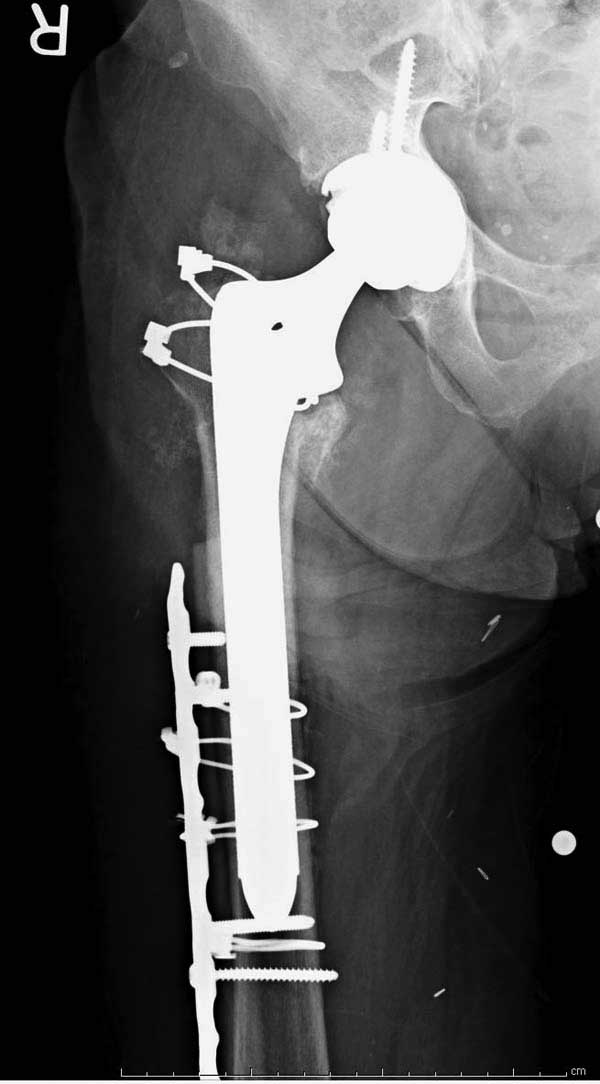

Такие “чужие осложнения” встречаются у всех и представляю банальный случай, который шаг за шагом показано как перерос в более сложный процесс... Больная 70 лет, множественные ко-морбидности, чрезвертельный перелом первоначально фиксирован Гамма 3. Осложнение в течение 6 недель, ревизия тотальной артропластикой и во время установки ножки обнаружена трещина диафиза (17), из малого доступа фиксация алло-графтом.

Обычно после чрезвертельных переломов, за исключением молодых, у пожилых остается нестабильность при движении. Часто падают и после 3х мес. в результате падения обнаружен перипротезный перелом (22-23), который зафиксирован Синтез пластиной.

Повторно поступает после двух с половиной лет, где обнаруживается перелом на второй стороне. Немного сложно, но для фиксации выбрали Antegrade InterTan Smith Nephew Nail и с момента фиксации более 3х мес.